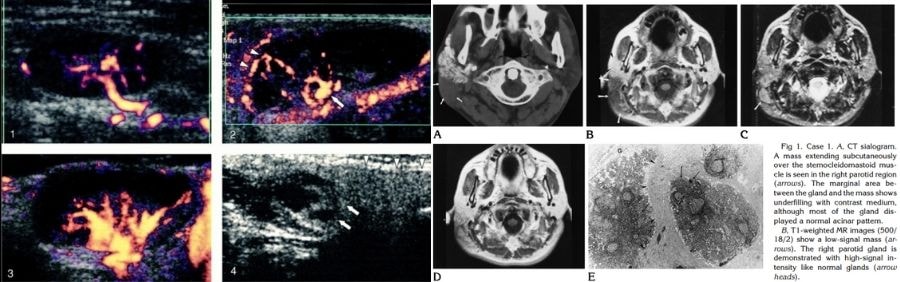

Đặc điểm nhận dạng chính của bệnh là sự xuất hiện của các khối u (nốt sần) mềm, phát triển chậm, không đau ở dưới da. Vị trí phổ biến nhất là vùng đầu và cổ, đặc biệt là khu vực tuyến nước bọt mang tai và các hạch bạch huyết lân cận.

Để đi đến kết luận chính xác, bác sĩ không thể chỉ dựa vào khám lâm sàng hoặc chẩn đoán hình ảnh (như siêu âm hay chụp CT). Tiêu chuẩn vàng để chẩn đoán Bệnh Kimura là sinh thiết (biopsy).

Bác sĩ sẽ lấy một mẫu mô nhỏ từ khối u để kiểm tra dưới kính hiển vi. Chỉ khi quan sát thấy các đặc điểm mô bệnh học đặc trưng, bác sĩ mới có thể tự tin loại trừ ung thư và xác định đó là Bệnh Kimura.